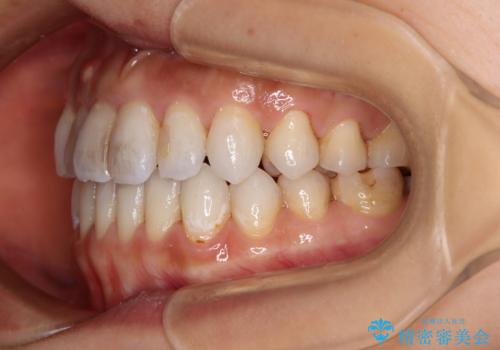

【モニター】開咬を治したい インビザラインによる矯正治療

- 上下前歯の開咬とデコボコを気にして来院された患者様です。

開咬(オープンバイト)はインビザラインによる矯正治療がワイヤー装置と比べて圧倒的に有利であるため、インビザラインによる矯正治療を行うこととしました。

通院されなかった時期があって治療期間が長くなったり、奥歯に抜歯が必要な歯があったりと、治療は一筋縄にはいきませんでしたが、何とか治療を終えることができました。